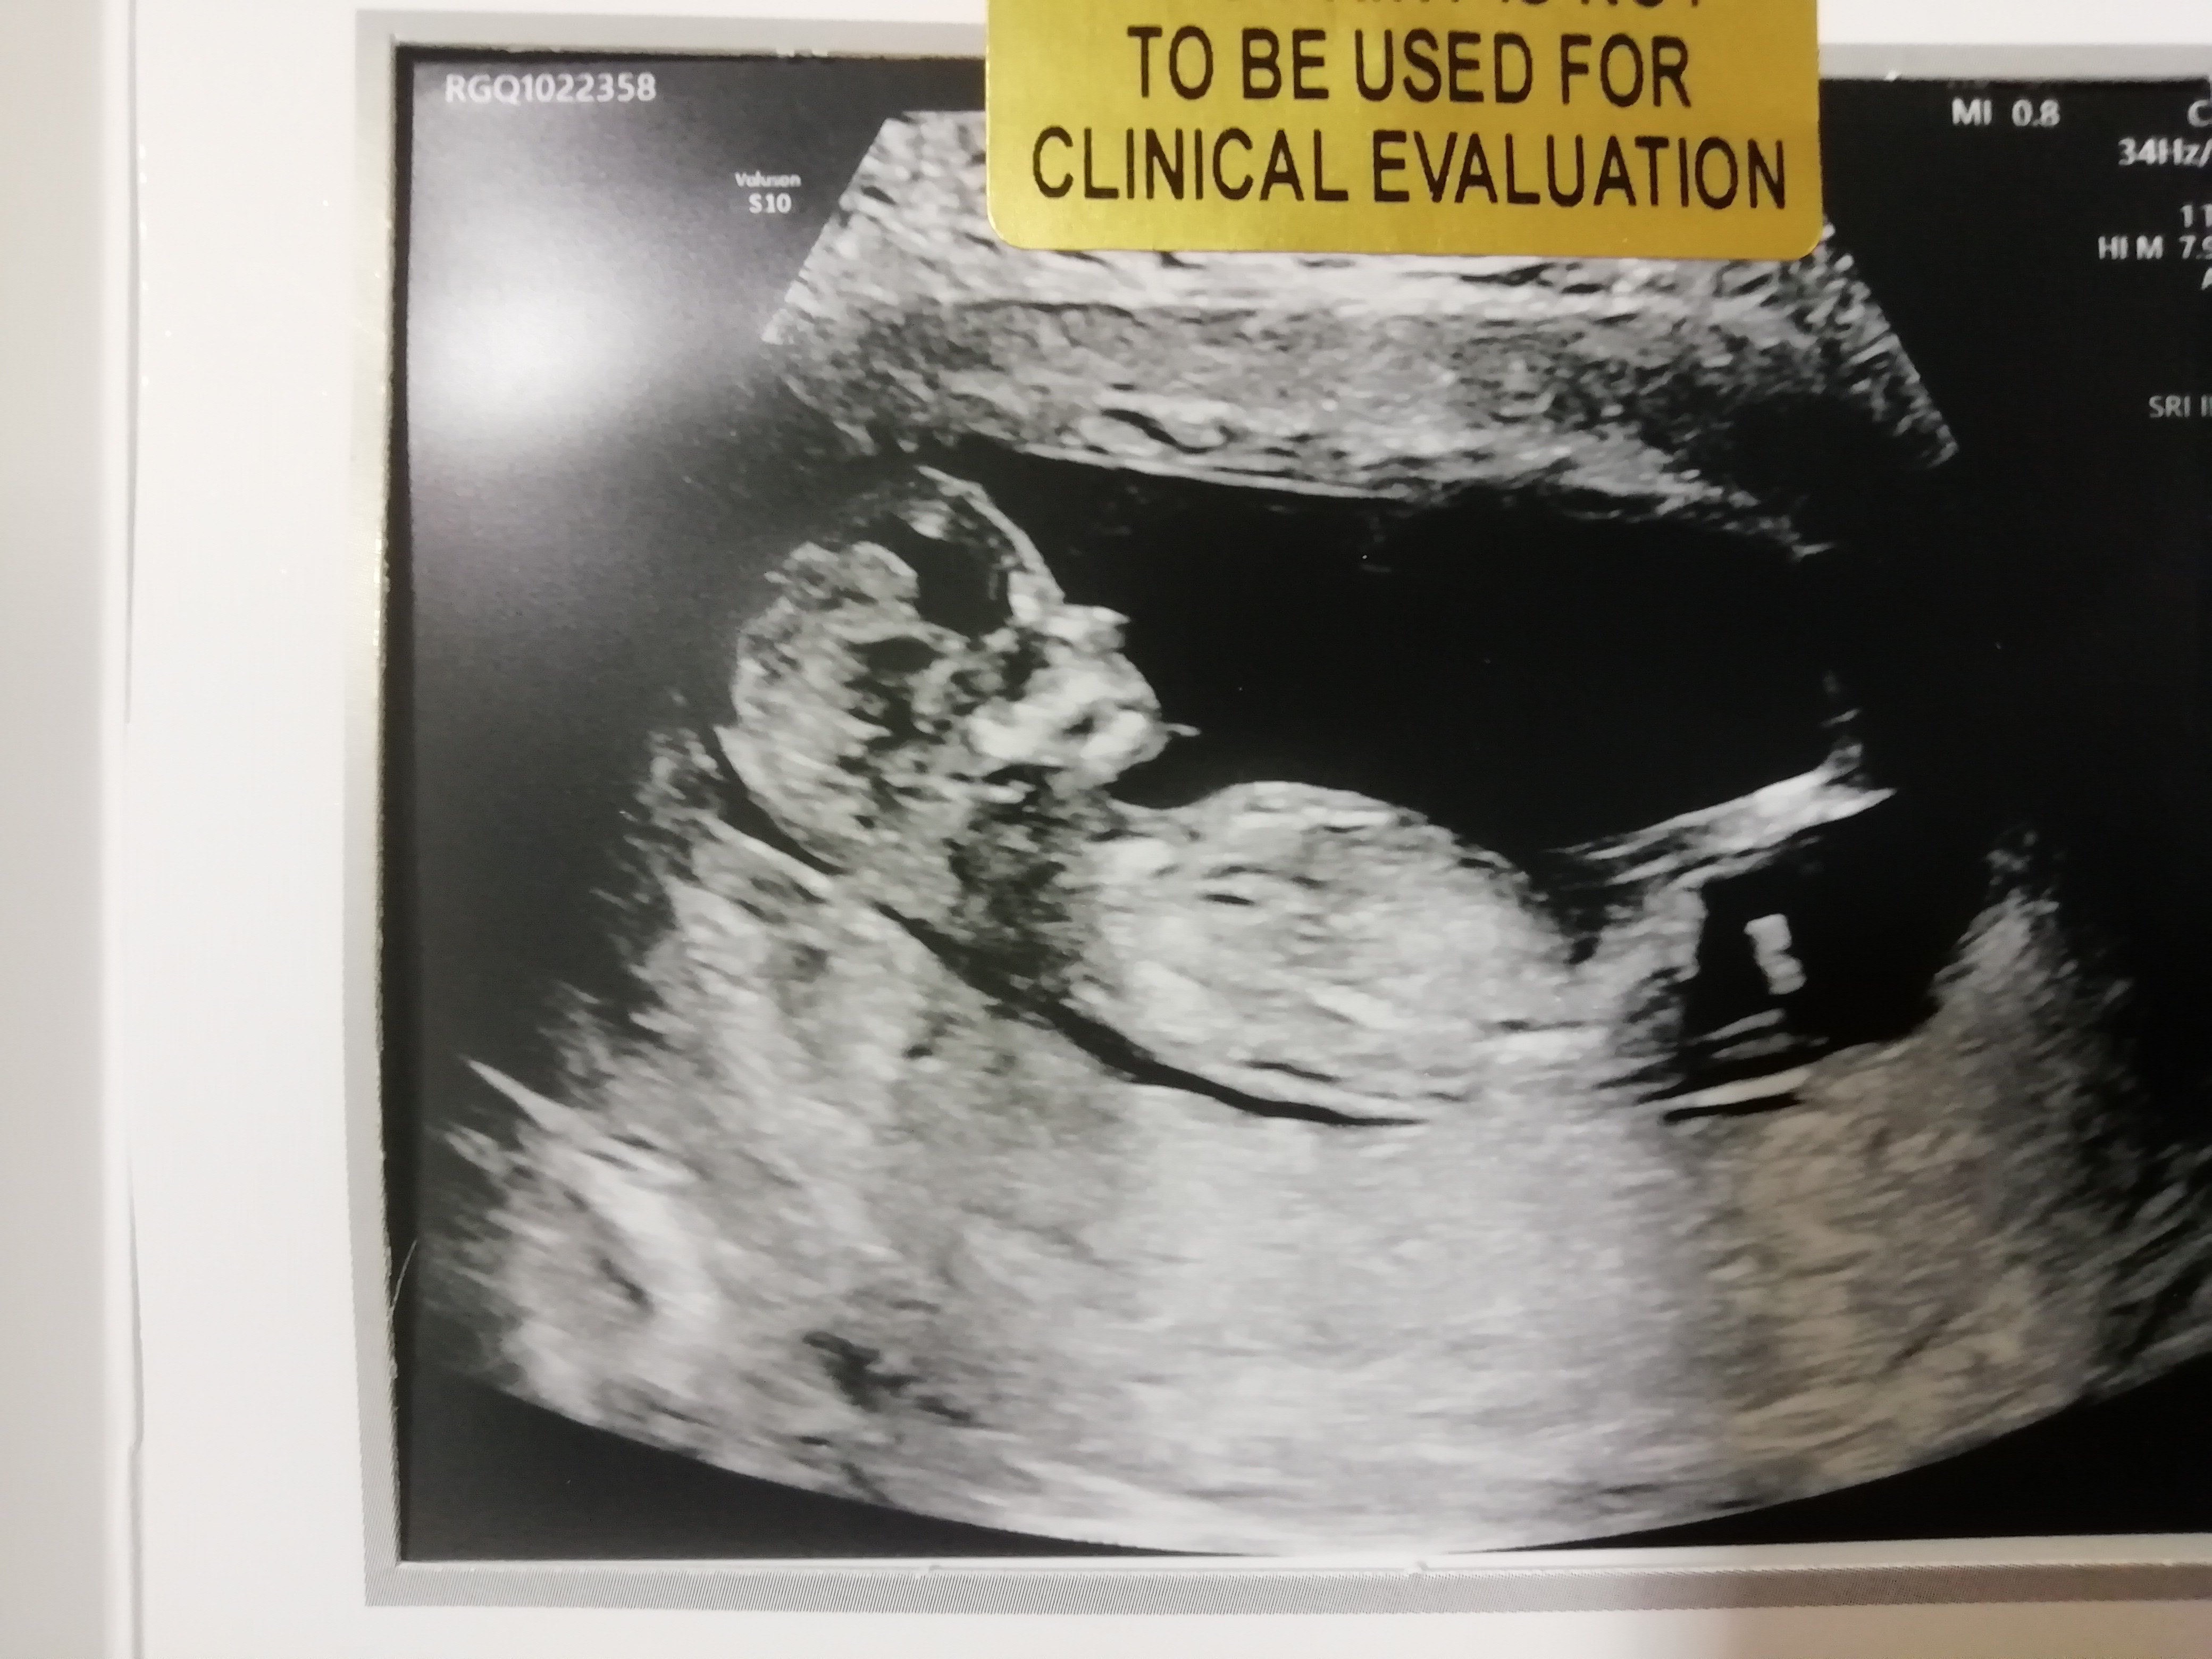

Ja po prenatalnych, wszystko ok, bejbik skakal ☺️ przeziernosc 1.7 12+4